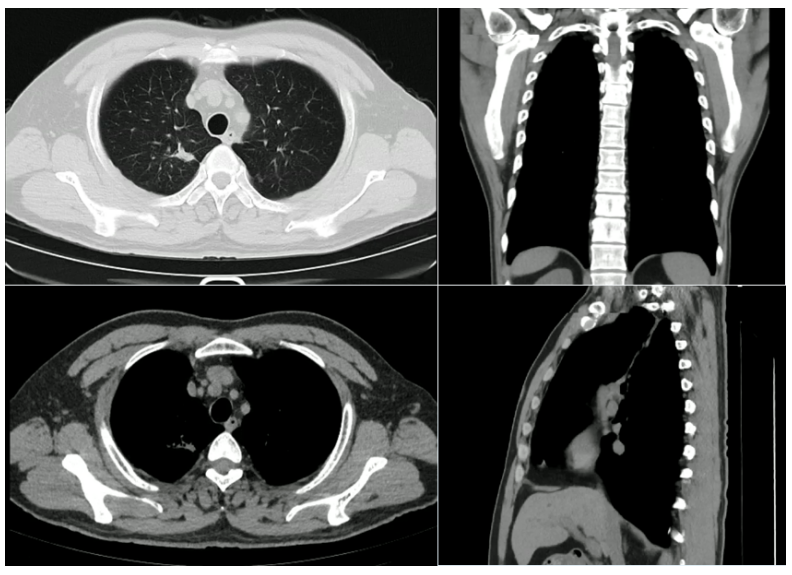

2023年12月11日(服药6周后)复查胸部CT:上肺肿块明显消退,仅残存一些小的纤维灶,额状面和矢状面变化明显(图7)

图片

7  患者胸部CT(2023年12月11日)

继续服药3个月,2024年3月11日再次复查胸部CT:病灶吸收良好,纵隔窗基本看不到病变(图8)

8  患者胸部CT(2024年3月11日)